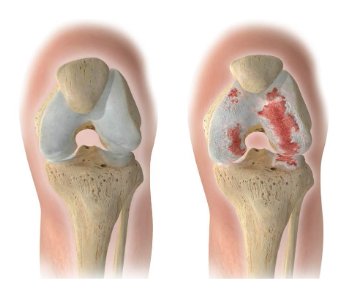

artrose do joelho, ou gonartrose, é uma doença degenerativa que provoca o desgaste progressivo da cartilagem, levando à dor, rigidez e perda de mobilidade. É uma das causas mais frequentes de dor no joelho, especialmente acima dos 50 anos.

A artrose significa desgaste da articulação, ou melhor, desgaste da cartilagem que reveste os ossos e permite a mobilidade do joelho sem atrito. Sem essa cartilagem para amortecer o choque, dobra e esticar o joelho assim como realizar carga com a joelho afectado provoca dor.